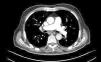

Una angio-TC torácica al ingreso mostraba signos de sobreinfección respiratoria con opacidades nodulillares en el vidrio deslustrado de predominio bibasal pero con afectación de todos los lóbulos y zonas de consolidación bibasales, sin signos de embolismo pulmonar (fig. 1).